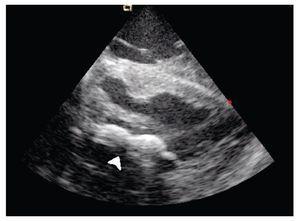

The transeptal puncture was performed under direct ultrasound guidance (Figure 1). After hemodynamic confirmation of left atrial curve morphology, the Mullins catheter was advanced and exchanged for a spiral guide-wire. Interatrial septum was dilated with the usual technique and an Inoue 28 balloon was advanced through the mitral valve into the left ventricle under direct ultrasound guidance (Figure 2). Mitral valvuloplasty at the level of the valve (Figure 3) was performed by a single inflation with the Inoue balloon with 28 ml of normal saline. ICE analysis across the mitral valve showed a significant drop of mean transmitral valve gradient and an increase of the mitral valve area, without an increase of mitral regurgitation.

Figure 2. Shows the Inoue balloon deflated (arrow) at the mitral valvular plane in a long-axis view of the left ventricle.